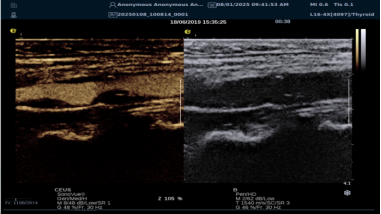

(一)RTSWE 实时剪切波弹性成像技术

RTSWE 技术源于对剪切波的创新研究,通过 MultiPush?超声触诊技术产生振动生成剪切波,OmniSound?平台提升帧频捕获信息并测量杨氏模量。其优势突出:

image.png

? 可视化,对颈动脉内膜和斑块实时弹性成像,彩色编码显示硬度,便于医生区分斑块类型。

? 定量测量方面,分析结果以kPam/s为单位测量颈动脉相关部位杨氏模量,毫米级分辨率显示微小病变,提供 20 余种参数综合评估斑块稳定性和血管硬化因测量取样范围可极度小甚至对于颈动脉内中膜硬度可定量测量,引发不同视角评价极早期动脉硬化评估,实属科研利器。

? 采用马赫圆锥脉冲激励技术,无需按压,减少检查者影响,帧频高、操作简便、耗时短。

RTSWE 是全球唯一的实时全幅全定量剪切波弹性成像系统,OmniSound?平台采集与显示帧频国际领先,对颈动脉结构定量分析和脑卒中早期预防意义重大。